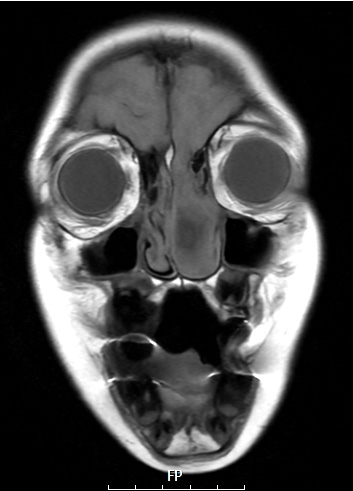

Washington University Experience | DEVELOPMENTAL MALFORMATIONS | Encephalocele - Nasal Glioma | 6A3 T1 THIN NoC (Case 6)

6A3,4 Direct connection of the intranasal brain tissue into the left nasal cavity as shown in T1 THIN (6A3) and T2 Haste (6A4) scans.